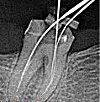

Оттаивание корневых каналов, запечатанных мягкими пастами, не составляет труда и осуществляется с помощью ручного инструмента. Различные растворители, обработка ультразвуком и борное бурение используются для удаления твердых зарядов. Канал постепенно и осторожно проходит от устья к вершине, используя файлы меньшего диаметра (иглы для прохода канала). Ультразвук и бор используются в тех случаях, когда невозможно пропустить канал вручную. Чаще всего трудности с ослаблением канала связаны с его анатомическим строением: изогнутый канал, узкий канал или щель.

Герметизация резорбированного канала представляет значительные трудности для стоматолога из-за того факта, что резорцин-формальдегидная паста после отверждения превращается в очень твердый материал. Поэтому для разрыхления используются сильные растворители, ультразвуковые насадки и отверстия. Стоматолог вводит каплю растворителя, затем с помощью ультразвука и бора немного «проникает» через заряд в канал, расширяет область и ополаскивает водой. Затем процедура повторяется. Чем глубже канал, тем меньше диаметр используемых инструментов. Спуск по резорцинированному каналу может быть довольно продолжительным и всегда сопряжен с риском перфорации зуба.